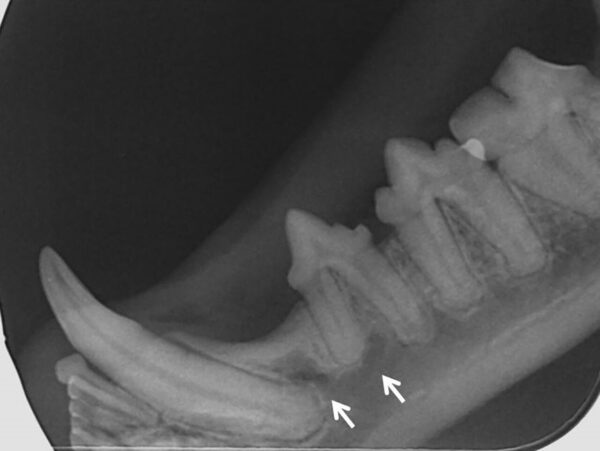

- Grado 4 (PD4): pérdida del soporte óseo mayor de un 50 % (imagen 9).

Además de permitirnos evaluar el grado de enfermedad periodontal, también hace posible seleccionar el mejor tratamiento en función de su patología y las posibles complicaciones, como las fracturas mandibulares iatrogénicas en perros de talla pequeña con enfermedad periodontal PD4 (imágenes 10 y 11).